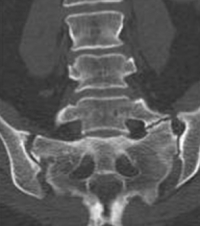

(Click to Enlarge) Series of degenerative cervical slips. Iatrogenic Instability of the Cervical Spine Overview This is an example of what can happen when the spine becomes unstable after [...]